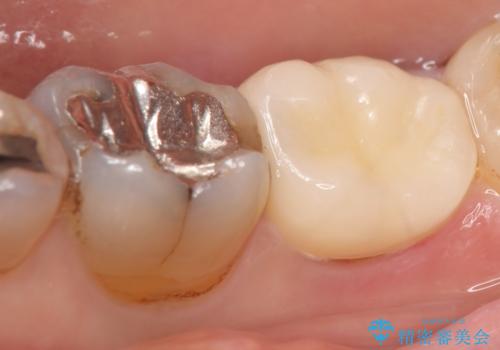

古い樹脂やカリエスを除去後、形を整え、オールセラミッククラウンによる補綴を行いました。

今回用いたオールセラミッククラウンはジルコニアフレームという白い素材の上にセラミックを盛っているため、審美性が非常に高いのが特徴です。

また、ジルコニアは人工ダイヤモンドの材料にも使われているほど高い強度を持っており、そのためオールセラミッククラウンは審美性だけでなく、奥歯やブリッジの補綴も可能とするクラウンです。